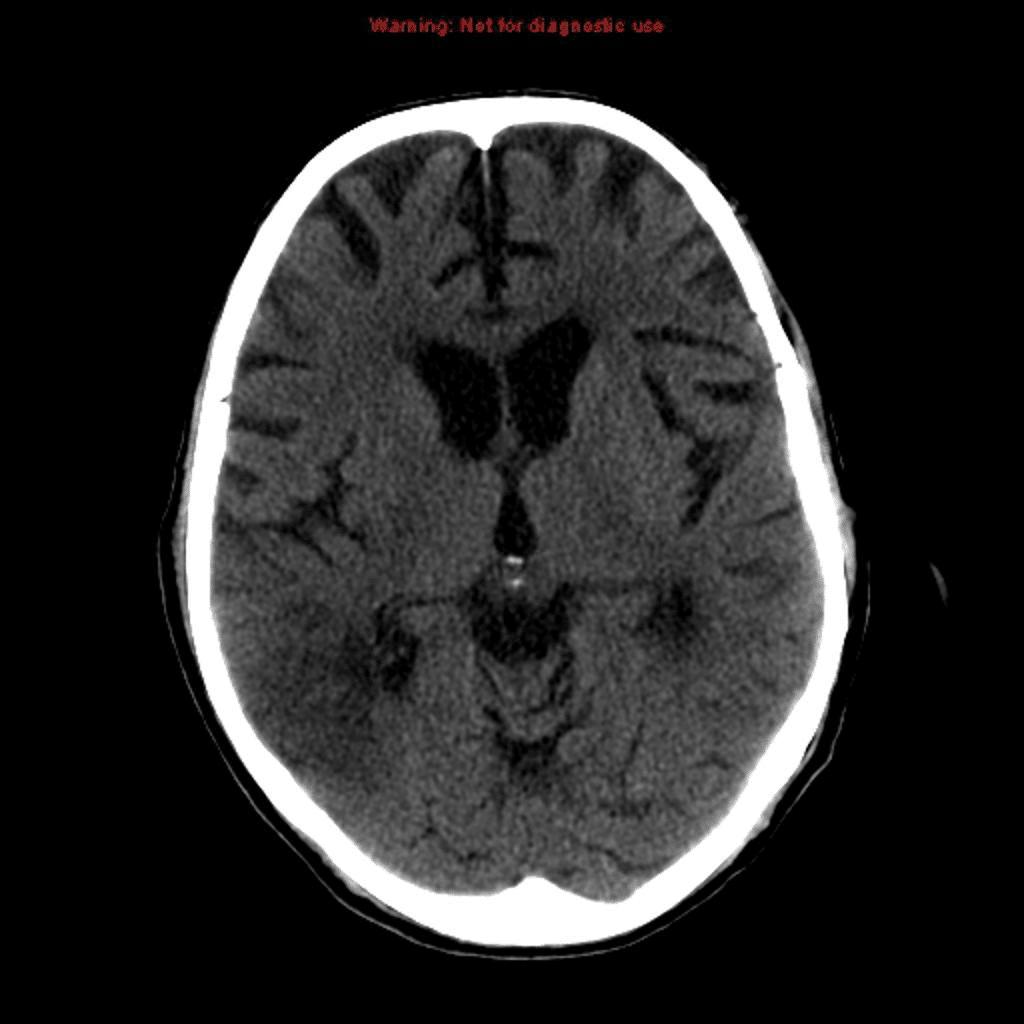

9. Question

9. A patient’s stroke symptoms began 2 hours ago. In the emergency department, she has the following CT scan of the head:

What is the next most appropriate step?